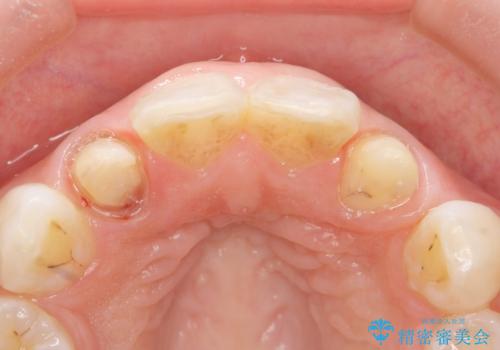

- 上の前歯の色と隙間を気にされ、来院された患者様です。

精査したところ、右上の側切歯(右上2)は神経が死んで変色しており、左上の側切歯と犬歯の間に2mm程度の隙間を認めました。

矯正せずに早く治したいという強いご希望により、セラミッククラウンによる補綴治療(上顎両側2の2本)を行いました。